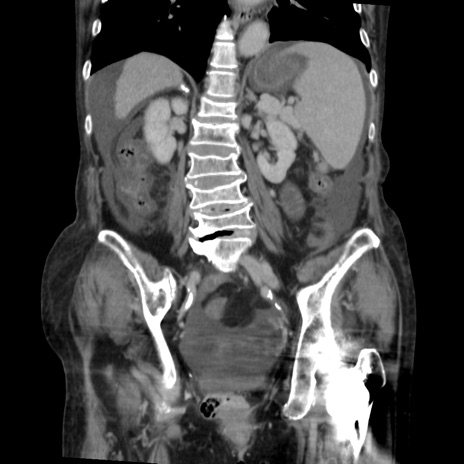

症例31(冠状断像)

【症例】80歳代 女性

【主訴】腹部膨満感

【現病歴】他院にて肝硬変にてフォロー中。1週間前から便秘、腹部膨満感、臍部腫瘤あり受診となる。

【既往歴】肝硬変

【身体所見】腹部膨隆あり、皮膚変化なし、疼痛なし。

【データ】WBC 4600、CRP 0.25